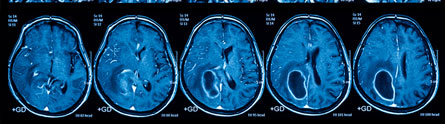

Brain tumours are the leading cause of cancer-related death in children and young adults. A major challenge to improving this outcome, is developing effective treatments that can cross the protective ‘blood brain barrier’ to directly target tumours in the brain.

Now, a new international consortium has been launched to bring together world-leading experts to take on this challenge, by exploring the use of novel drug delivery systems to physically bypass the blood brain barrier.